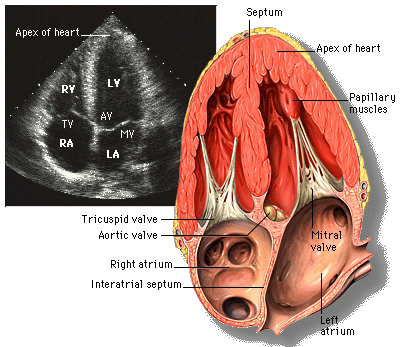

• Cardiac Echocardiography: Basics and Uses

• Anatomy and Physiology of the Heart